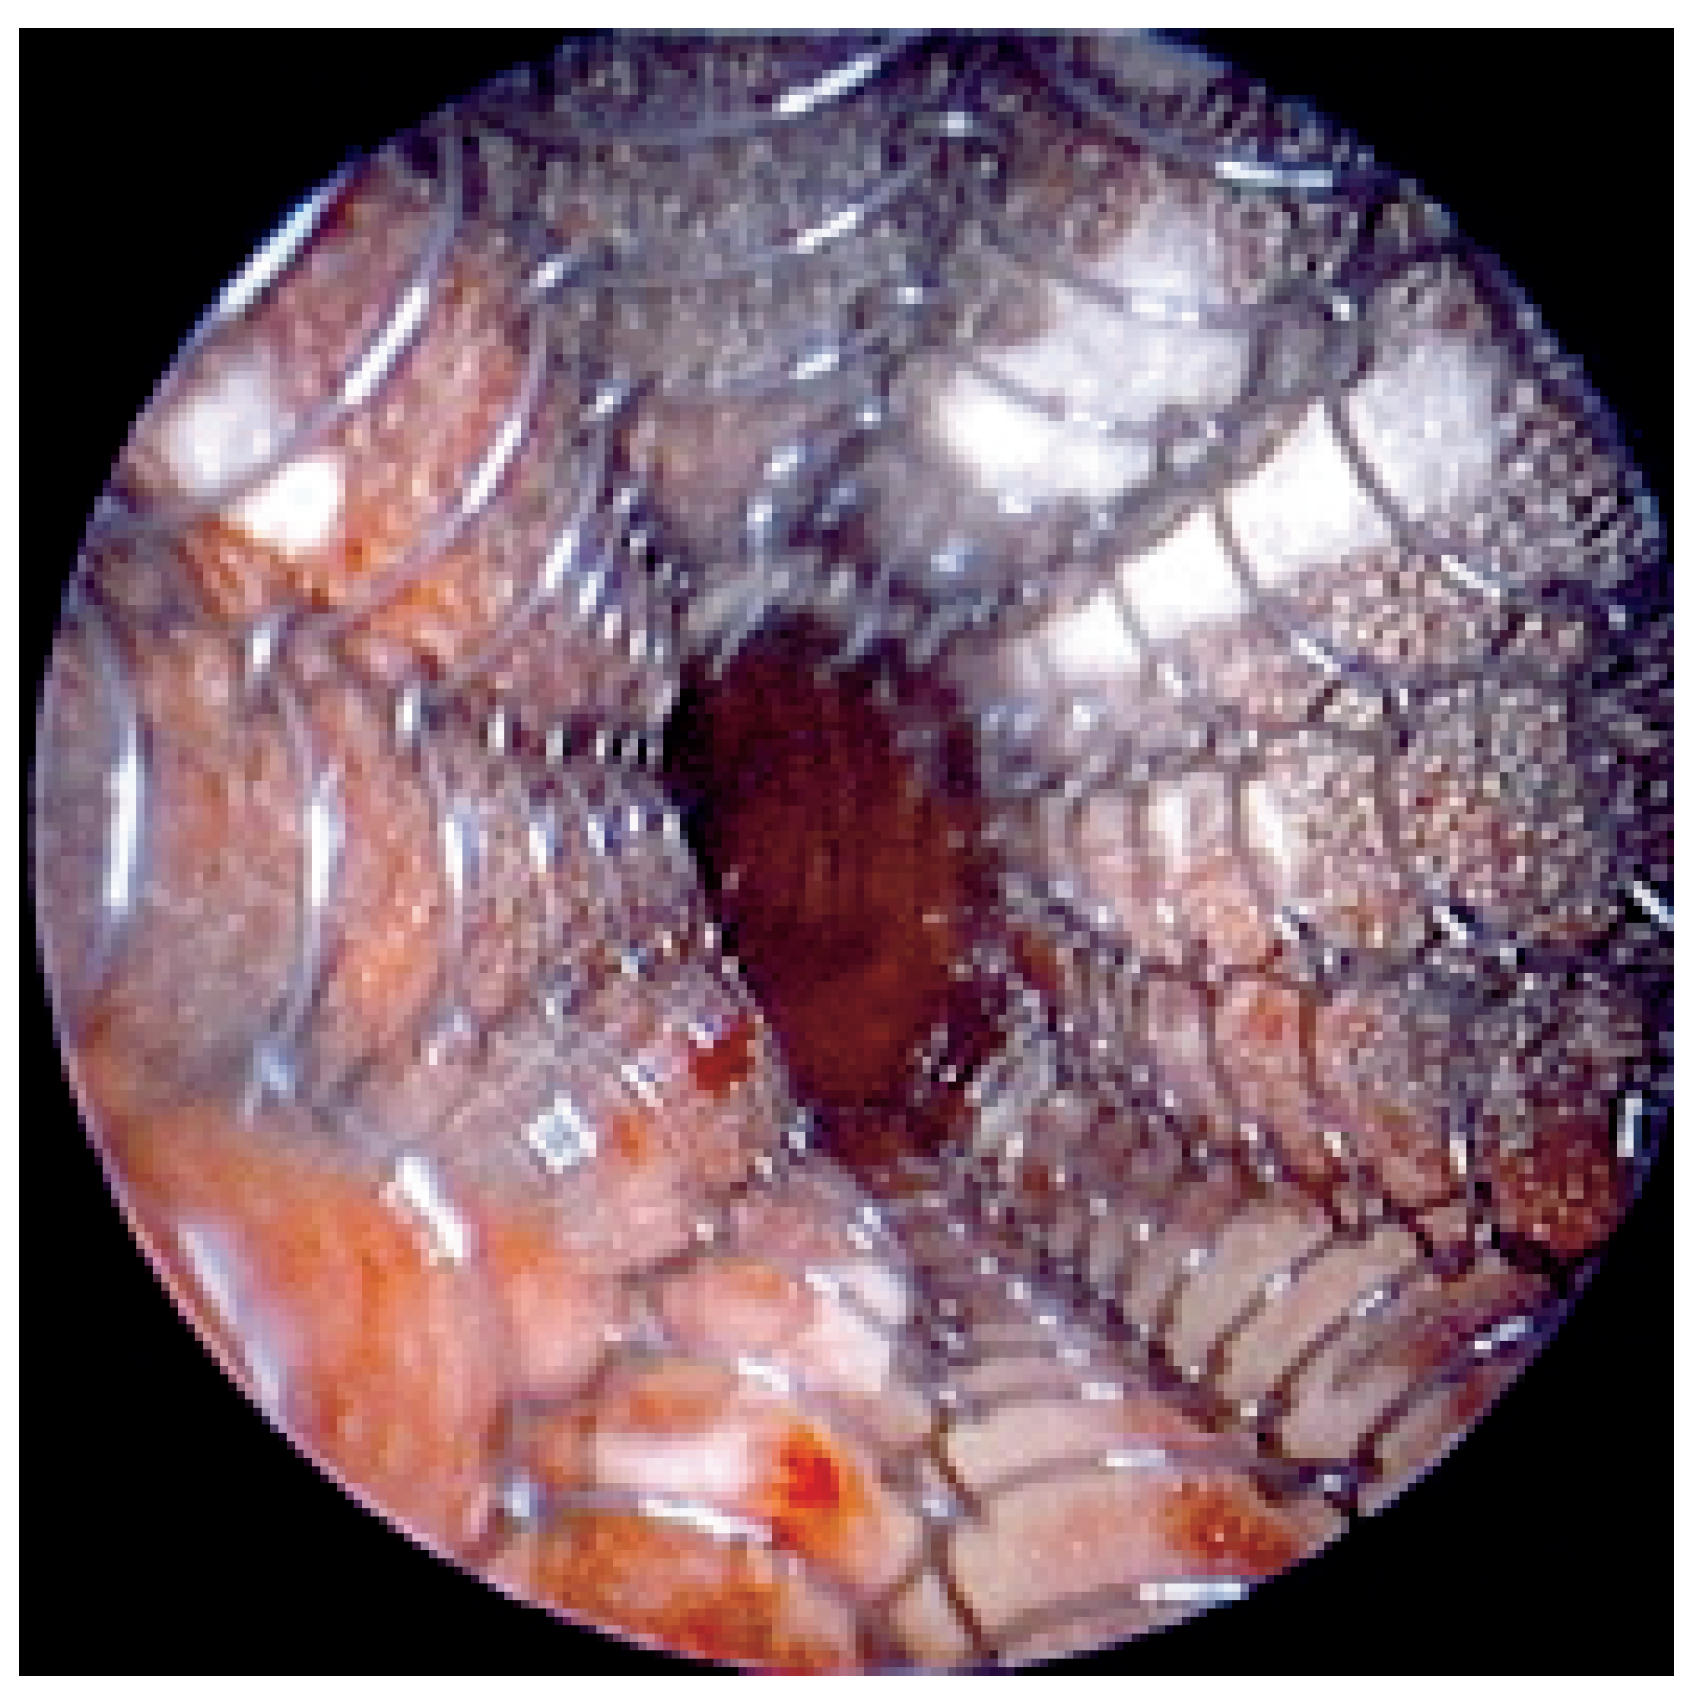

Abbildung 1. Hochgradige Trachea-Stenose beim Plattenepithelkarzinom. Der Pfeil markiert das freie Lumen.